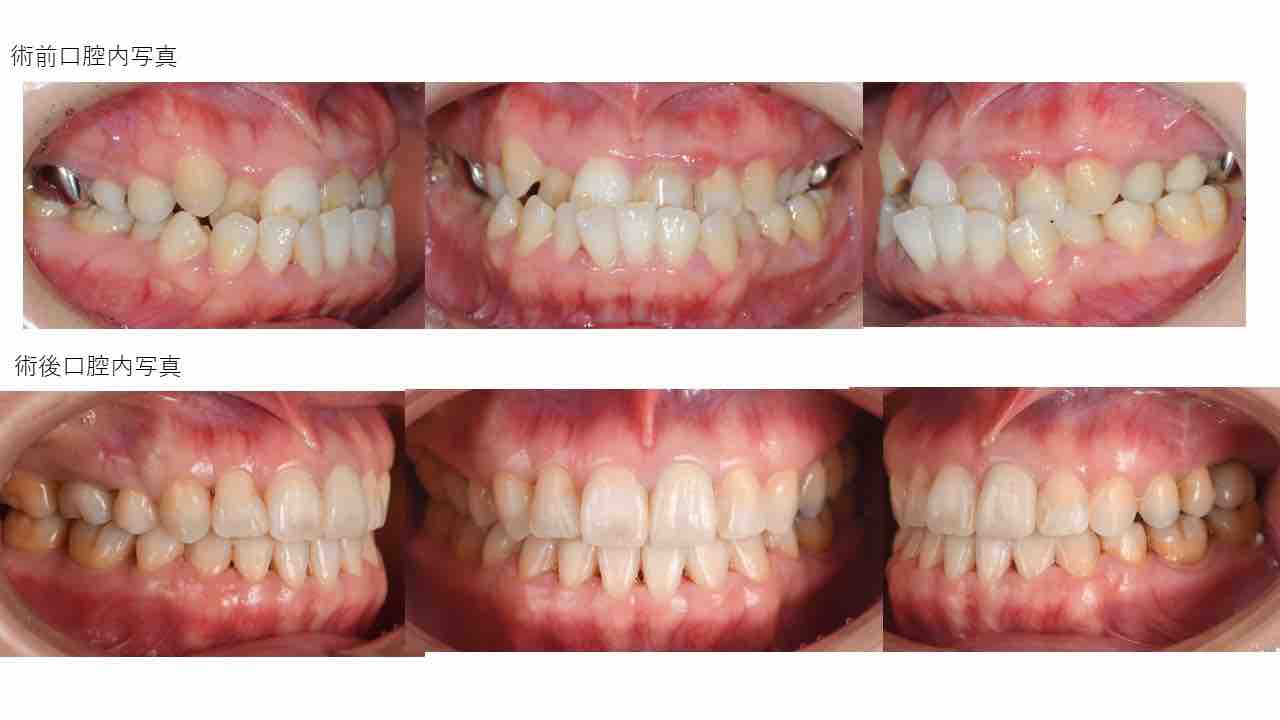

Èþ¤·¤¤¸ý¸µ¤Ë¡¡Ã°Ìî»õ²Ê¶ºÀµ¼£ÎŪ

Èþ¤·¤¤¸ý¸µ¤Ë¡¡Ã°Ìî»õ²Ê¶ºÀµ¼£ÎÅ©

Èþ¤·¤¤¸ý¸µ¤Ë¡¡Ã°Ìî»õ²Ê¶ºÀµ¼£ÎŨ

Èþ¤·¤¤¸ý¸µ¤Î¡¡Ã°Ìî»õ²Ê¶ºÀµ¼£Îŧ

Èþ¤·¤¤¸ý¸µ¤Ë¡¡Ã°Ìî»õ²Ê¶ºÀµ¼£ÎŦ

Èþ¤·¤¤¸ý¸µ¤Ë¡¡Ã°Ìî»õ²Ê¶ºÀµ¼£ÎÅ¥

Èþ¤·¤¤¸ý¸µ¤Ë¡¡Ã°Ìî»õ²Ê¶ºÀµ¼£ÎŤ

Èþ¤·¤¤¸ý¸µ¤Ë¡¡Ã°Ìî»õ²Ê¶ºÀµ¼£ÎÅ£

Èþ¤·¤¤¸ý¸µ¤Ë¡¡Ã°Ìî»õ²Ê¶ºÀµ¼£ÎÅ¢

Èþ¤·¤¤¸ý¸µ¤Ë¡¡Ã°Ìî»õ²Ê¶ºÀµ¼£ÎÅ¡